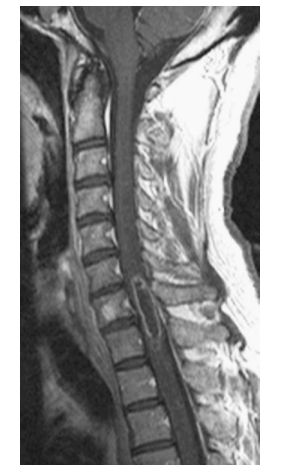

A 32-year-old recent immigrant from Southeast Asia presents with back pain and a new kyphotic deformity after tripping upin his flat. T1 and T2 W MRI are shown.Which one of the following is most likely diagnosis?

e. Spinal tuberculosis

Tuberculosis is the most common granulomatous

infection of the spine. The three patterns of spinal

involvement are peridiscal (commonest), central,

and anterior. Peridiscal occurs adjacent to the vertebral endplate and spreads around a single intervertebral disc as the abscess material tracks

beneath the anterior longitudinal ligament (the

disc is usually spared unlike in pyogenic infections). Central involvement occurs in the middle

of the vertebral body and eventually leads to vertebral collapse and kyphotic deformity. This pattern of involvement can be mistaken for a

tumor. Anterior infections begin beneath the anterior longitudinal ligament, causing scalloping of the anterior vertebral bodies, and extend over multiple levels. The presentation is highly variable.

Mild back pain is the most common symptom.

Patients with tuberculous infections may present

with malaise, fevers, night sweats, and weight loss.

In addition, chronic infections may result in cutaneous sinuses, neurologic deficits (in up to 40% of patients), and kyphotic deformities. Certain factors define the high-risk population and should raise suspicion. Patients from countries with a high incidence of tuberculosis, such as Southeast Asia,

South America, and Russia are considered high

risk. Patients who live in confinement with others,

such as homeless centers and prisons, are also at

risk. Elderly adults, chronic alcoholics, patients

with AIDS, and patients with a family member

or a household contact with tuberculosis are additional high-risk groups. The leukocyte count may be normal or mildly elevated. The ESR is mildly

elevated (typically <50), but may be normal in

up to 25% of cases. Although the purified protein

derivative (PPD) skin test may detect active infection or past exposure, this test is unreliable because false-negative results may occur in malnourished and immunocompromised patients. Anergy panel testing should be included for this reason. Urine cultures, sputum specimens, and gastric washings may be helpful for diagnosis if the primary source is unknown. The most reliable test for diagnosis is CT-guided biopsy. The characteristic finding on histology is a granuloma, which is described as a multinucleated giant-cell reaction surrounding a central region of caseating necrosis. Molecular detection of mycobacterium DNA or RNA is useful for rapid diagnosis and for determining drug resistance. Radiographs: A clue to diagnosis is the presence of extensive vertebral destruction out of proportion to the amount of pain. Typically, the intervertebral discs are preserved in the early stages of this disease. Chest radiographs can be useful in demonstrating pulmonary MRI: The imaging modality of choice for diagnosis of spinal TBCT: Plays a role in defining the extent of bony destruction and localization for biopsies. Chemotherapy (four-drug regimen, for a minimum of 6-month duration, includes isoniazid, rifampin, pyrazinamide, and ethambutol) and brace immobilization are the initial treatment except in patients presenting with neurologic deficit or progressive deformity. The indications for surgery and the principles of surgical reconstruction are similar to those advised for pyogenic spinal infections.